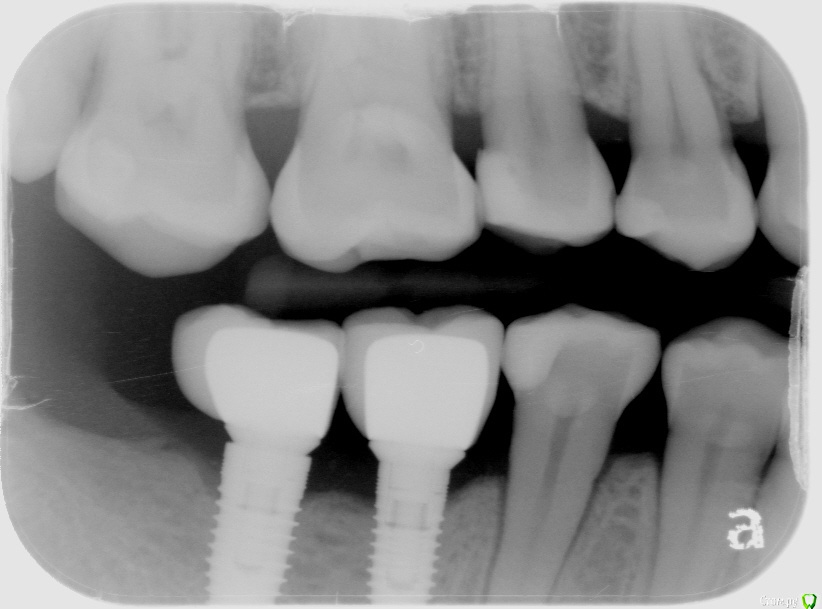

Natalia105 Опубликовано 6 апреля, 2017 Поделиться Опубликовано 6 апреля, 2017 Здравствуйте уважаемые врачи. У меня установлены три импланта в июне 2016 года - на зубы 19, 30 и 31, прижились хорошо. При попытке установки коронок выяснилось, что коронки слишком маленького размера (импланты 30 и 31 стоят слишком близко друг к другу и нет достаточно места чтобы сделать коронки крупнее). Между десной и коронками в глаза бросается металл. Выглядит все это ужасно некрасиво и неестественно. Доктор уверяет меня, что красота в молярах это не главное, а главное это функциональность. Но разве одно с другим несовместимо? Тем более за такие деньги... Да и маленькие коронки тоже ведь снижают функциональность. Коронки сделали только в марте, потому что ждали снятия брекетов. Я пока отказалась от установки таких коронок до выяснения следующих вопросов: 1. Размеры коронок 30 и 31 зубов слишком маленькие, так как недостаточно места. Импланты стоят слишком близко друг к другу, что это - ошибка доктора? Он делал операцию "на глазок" без шаблона (возможно потому, что у меня в тот момент были брекеты). На мои претензии доктор ответил, что кость в том месте мягкая и он не мог поставить 31 имплант дальше. Хотя другой доктор до этого говорил, что с костью у меня там все в порядке (я делала 3D рентген)... Но ведь если кость там действительно мягкая - доктор должен был нарастить ее, не так ли? Потом поставить туда широкий имплант + индивидуальный абатмент, и в итоге коронку нормального размера (это ведь моляр). Так ведь, или я ошибаюсь? 2. В моей ситуации (если не удалять импланты) можно и нужно ли сделать на 31 зуб широкий индивидуальный абатмент и более длинную коронку? При этом с нормальной нагрузкой на имплант (чтобы не расшатался) и чтобы коронка не сломалась под нагрузкой? Или как вариант - одну большую длинную коронку на два импланта? 3. На рентгене видно, что импланты 30 и 31 недостаточно покрыты костью - нужно ли нарастить кость? Или и так сойдет? Если оставить так - не будет ли рецессия кости и не приведет ли в скором времени к потере импланта? 4. Между десной и коронками в глаза бросается металл. Доктор уверял меня, что наращивать десну мне не нужно, потому что там будут скапливаться бактерии (между коронкой и десной), что приведет к воспалению десны и другим неприятным последствиям. Так ли это? Но ведь если десну не нарастить, то на торчащий абатмент будет наматываться еда (особенно мясо) - что тоже неприятно и возможно больно. Да и выглядит неэстэтично... Что же мне делать - наращивать десну или нет? 5. Если оставить 30 и 31 коронки такими маленькими, то имеет ли смысл тогда сделать еще один имплант на 32-й зуб? Во-первых, чтобы продлить зубной ряд - жевательная способность улучшится, во-вторых, нагрузка на 30 и 31 уменьшится (меньше вероятности, что коронка 31-го зуба сломается или расшатается сам имплант 31-го зуба). Ссылка на комментарий

АнтонТЛТ Опубликовано 7 апреля, 2017 Поделиться Опубликовано 7 апреля, 2017 Десной и костью тут особо не помочь. Эстетику можно сделать цельно-цирконевыми абатментами (если они есть на эту систему). Еще один имплантат можно доставить. Ссылка на комментарий

Bier Опубликовано 8 апреля, 2017 Поделиться Опубликовано 8 апреля, 2017 удалить 1 имплантат и сразу поставить рядом другой. Но металлическая полоска возможно останется, а может и возможно еще отфрезеровать абатмент.антибиотики можно не принимать, не тот объем чтобы их прием был обязателен. Ссылка на комментарий